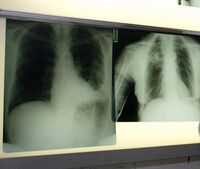

Morosini (AstraZeneca): "Bene nuove indicazioni osimertinib in cancro polmone"

Il via libera di Aifa alla rimborsabilità di osimertinib più chemioterapia nel trattamento in prima linea dei pazienti con carcinoma polmonare metastatico... continua a leggere